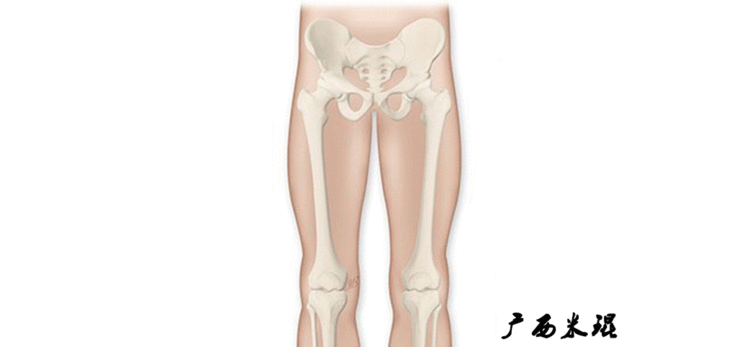

最常见的下肢畸形发生于冠状面,即膝内外翻畸形,冠状面的对线异常通过应用“对线异常检验”进行分析,机械轴的偏移(MAD)表现为对线异常。

膝内翻是指下肢力线通过膝关节中心点内侧,距中点2mm以上,偏内超过15mm为显著膝内翻。膝外翻是指下肢力线通过膝关节中心点外侧,距中点2mm以上,偏外超过10mm为显著膝外翻。